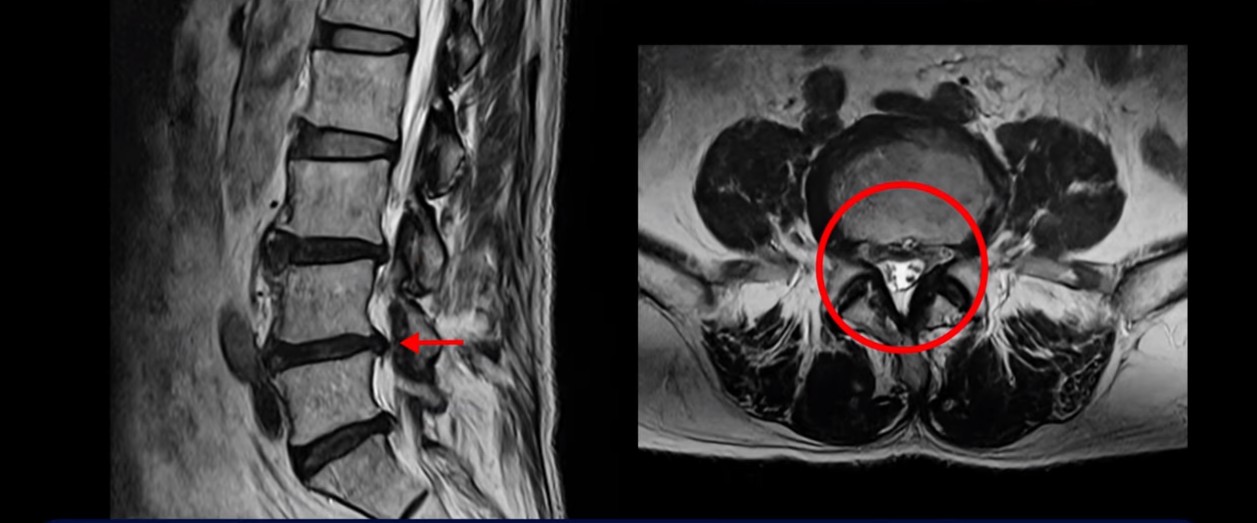

이분 MRI를 보면서 간단히 설명 드린 후 어떻게 허리에서 신경이 눌려서 발목이 마비된 환자가 수술 없이 치료가 될 수 있는 건지, 또 치료는 구체적으로 어떻게 하는 건지 자세히 설명 드리겠습니다.

이분은 허리디스크 탈출도 있고 중심성 협착도 있습니다.

4번 5번 중심성 협착을 보면 왼쪽 황색인대가 오른쪽에 비해 많이 두꺼워져 있습니다.

이 밀려나온 디스크는 최근 발생한 게 아니고 오래 전 발생하여 이미 굳어버린 디스크 수핵으로 보입니다. 보시다시피 앞에서는 밀려나온 디스크 뒤쪽에서는 두꺼워진 황색 인대가 신경을 눌러 발목마비가 온 걸로 보입니다.